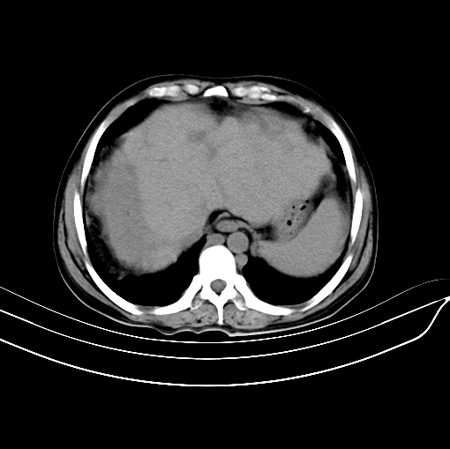

以下是引用江尾海头在2007-9-7 19:01:00的发言:[br]肝叶比例失调,肝边缘高低不平,尾状叶增大,肝裂增宽。肝右叶见较大密度减低影,边缘欠清。脾脏明显增大,胃底及奇静脉半奇静脉曲张。胆囊未见明显显示。 考虑:1、肝癌。2、肝硬化伴脾大静脉曲张。

以下是引用zhangxu5888在2007-9-7 22:31:00的发言:[br]1、肝硬化,食管 胃底及奇静脉半奇静脉曲张;2、脾脏肿大; 3、肝右叶的病灶呈锲性改变,内可见条片状钙化,边界清晰,密度明显低于周围正常肝组织,我觉得肝癌可能性不是很大, 同意楼上观点,有可能是栓塞,建议增强.